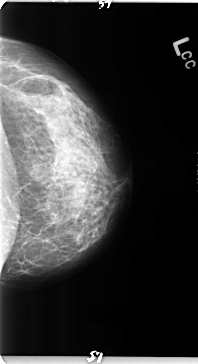

B_3132_1.LEFT_MLO

B_3132_1.LEFT_CC

LEFT_MLO LINES 4728 PIXELS_PER_LINE 2792 BITS_PER_PIXEL 12 RESOLUTION 50 NON_OVERLAY

LEFT_CC LINES 4728 PIXELS_PER_LINE 2568 BITS_PER_PIXEL 12 RESOLUTION 50 NON_OVERLAY